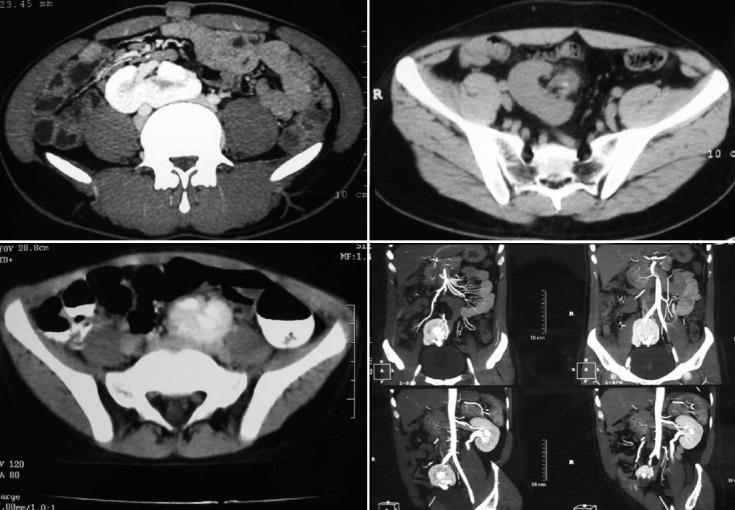

Eleven patients were evaluated. The mean age was 28.6 years (range 7 to 50). The presentation included stone disease in six, pelvi-ureteric obstruction in three, and as part of the evaluation for other causes of lower abdominal pain, it was found in two. A CT scan performed on eight patients did not show any evidence of fascia, while surgical exploration done on seven showed a well-defined fascial layer, at least on the ventral aspect of the kidney. A literature search also did not show any information about Gerota's fascia in the pelvic kidney.

共评估了11例患者。平均年龄为28.6岁(范围7至50岁)。临床表现包括6例结石病、3例肾盂输尿管梗阻,另外2例是在评估下腹部疼痛的其他原因时发现的。8例患者进行的CT扫描未显示任何筋膜存在的证据,而7例患者进行的手术探查显示至少在肾脏腹侧有一层界限清晰的筋膜。文献检索也未发现关于盆腔肾中肾周筋膜的任何信息。